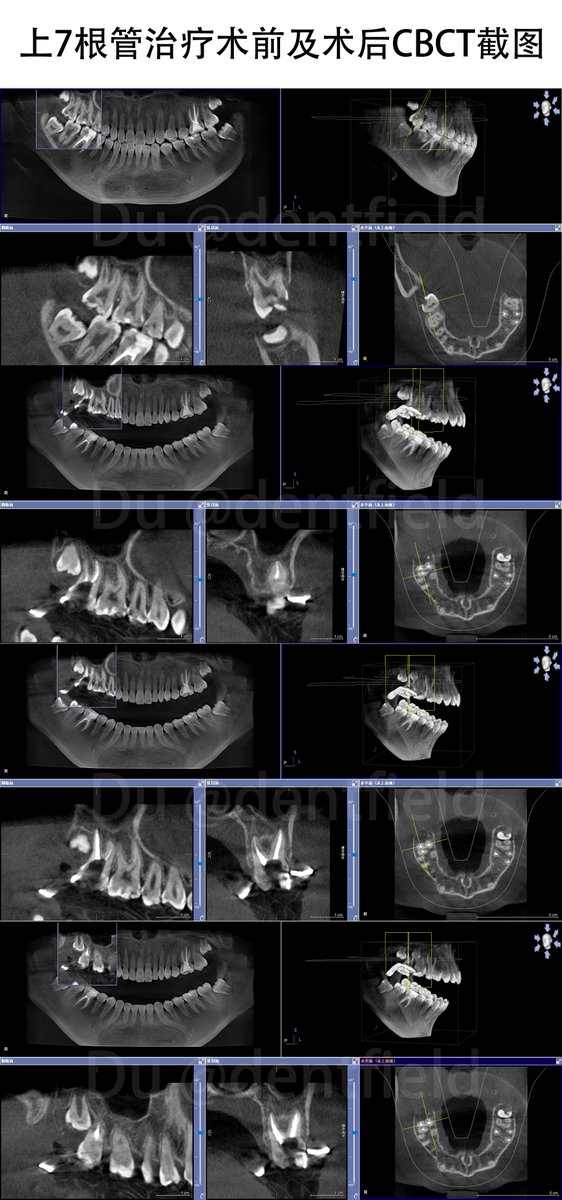

患者是个十几岁的小女孩,根管治疗后简单补个牙,竭尽全力保留天然牙😜

lufie🐼 tweet medialufie🐼 tweet media